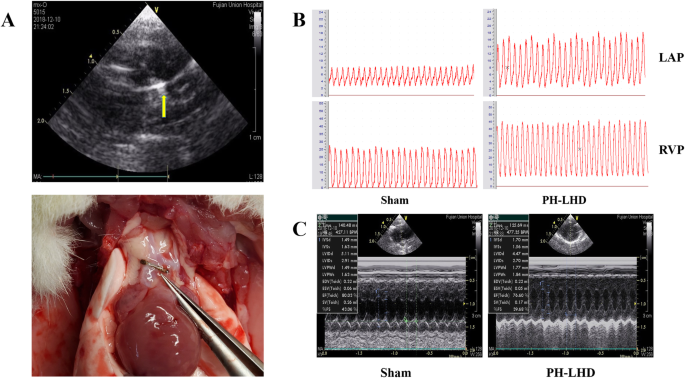

On day 25, echocardiography showed no significant movement of the metal clamp (Fig. 2a). Right ventricular pressure (RVP) monitoring can effectively reflect pulmonary pressure, and left atrial pressure (LAP) monitoring can reflect the disease progression of PH-LHD. In this study, RVP and LAP in the PH-LHD group were higher than those in the sham group (Fig. 2b, Table 2) (P < 0.05). The ratios of heart weight (HW) to body weight (BW) and left ventricular (LV) + ventricular septum (VS)/right ventricular (RV) in PH-LHD group was greater than those in the sham group (Table 1) (P < 0.05). IVSD and LVPWd in the PH-LHD group were greater than that in the sham group, LVIDd and EF in PH-LHD group were less than those in the sham group (P < 0.05). There were no significant differences in heart rate (HR) between the PH-LHD group and the sham group (Fig. 2c, Table 2).

a Establishment of the PH-LHD model. The metal titanium clip (yellow arrow) was located at the ascending aorta of rats in the PH-LHD group by Doppler echocardiography. The PH-LHD model was established, and the position of the titanium clip was shown in the ascending aorta above the coronary artery. b RVP and LAP were determined in PH-LHD model rats. Representative images of RVP and LAP in sham and PH-LHD model rats are shown (P < 0.05). c Doppler echocardiography of left cardiac function in PH-LHD model rats. Representative images of left ventricular dysfunction in rats were assessed by Doppler echocardiography. a Sham model b PH-LHD model